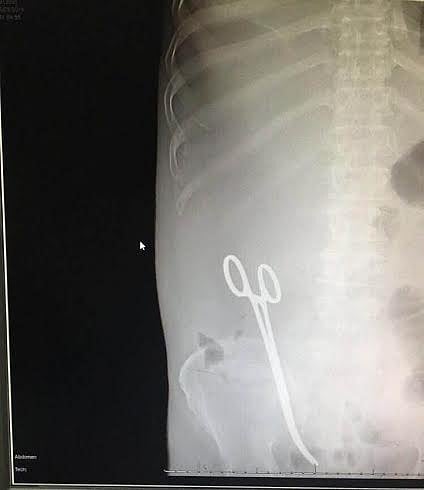

وقع طبيب مقيم "تحتفظ "سبق" باسمه" في خطأ طبي خطير عندما نسي مقصا في بطن مريضه الذي أجرى له عملية سحب سوائل الأسبوع الماضي.

وواصل: إلا أن الطبيب طمأنني  أنها  طبيعية ,حتى طلب مني إجراء أشعة ,وتبين من خلالها وجود  مقص العملية السابقة قد نسيه في بطني, ومباشرة أخبرني الطبيب بأنه يجب إجراء عملية أخرى لغسيل البطن ,وطلب مني التوقيع على ورقة مكتوبة باللغة الإنجليزية ,فوقعت لثقتي في الطبيب ,إلا أنه بعد إجراء العملية اليوم تبين ,استخراجهم لمقص, ولم يكن إجراء العملية لتنظيف بطني كما أخبرني.